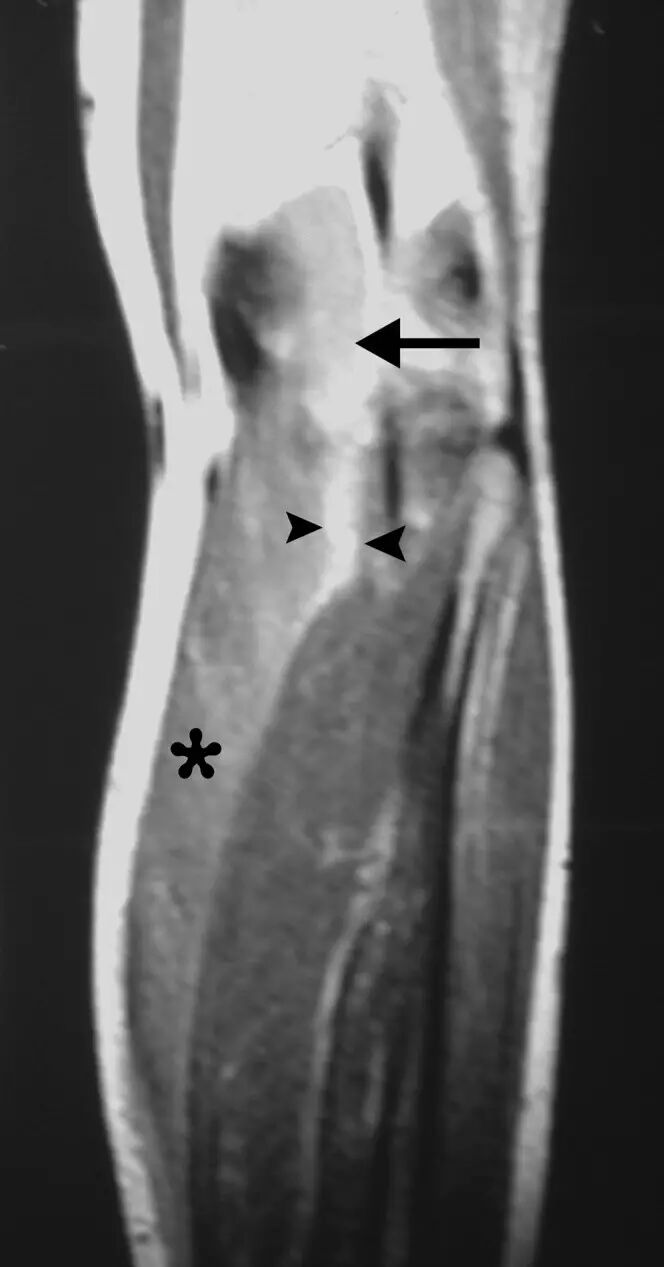

图5.一名13岁男性的横纹肌溶解症患者,在进行强烈的举重锻炼后,手臂上逐渐出现疼痛。(a)左臂的轴向T1加权的MR图像显示在三头肌肱肌的中间头中微小的增强的信号(星号)。(b)通过上臂的矢状T2加权的MR图像显示肱三头肌(箭头)中的弥散增加的信号强度。注意,水肿样的信号轨迹沿着肌肉束,假设反映肌肉结构的特征性羽毛状外观(箭头)。 相关性肌红蛋白尿证实了左肱三头肌的劳损性横纹肌溶解的诊断。

![]()